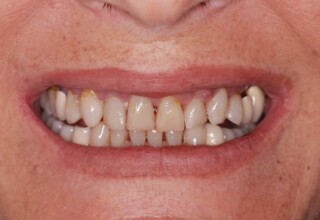

Οι όψεις πορσελάνης είναι ο καλύτερος τρόπος αντιμετώπισης αισθητικών προβλημάτων στην πρόσθια περιοχή του στόματος. Συνδυάζουν συντηρητική αφαίρεση οδοντικής ουσίας και πολύ υψηλή αισθητική απόδοση. Στο παρακάτω εκτεταμένο περιστατικό υπήρχαν: παλαιά σφραγίσματα, δυσχρωμίες, κακό σχήμα και μήκος δοντιών, κακή αναλογία δοντιών-ούλων. Έγινε προσεκτικός εργαστηριακός σχεδιασμός σε εκμαγεία απ’όπου προέκυψαν προσωρινές όψεις που τοποθετήθηκαν στο στόμα για δοκιμή και διορθώσεις. Όταν οριστικοποιήθηκαν οι μετατροπές, οι προσωρινές χρησιμοποιήθηκαν σαν οδηγός για τις μόνιμες. Οι πέντε μόνιμες όψεις πορσελάνης που κατασκευάστηκαν για τα πέντε πρόσθια δόντια της άνω απεκατέστησαν σχεδόν άψογα την αισθητική εμφάνιση της ασθενούς.

Αρχική εμφάνιση

Τελική εμφάνιση